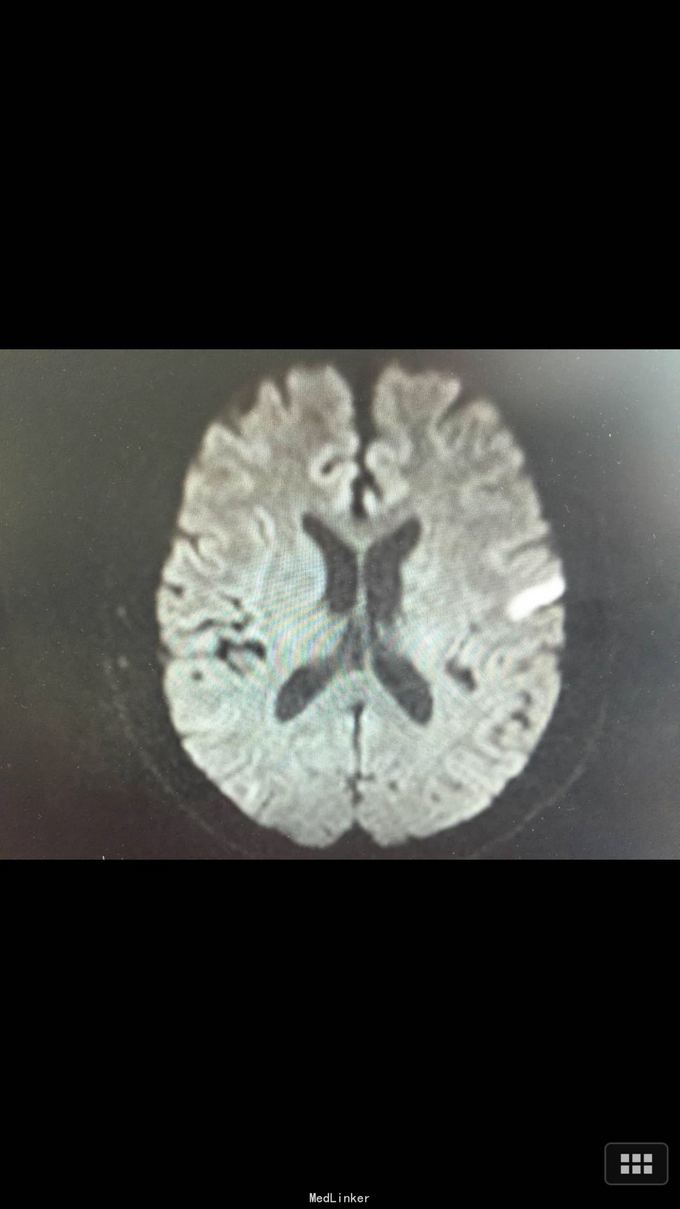

查体:BP:140/100mmHg,心肺腹无异常,神志清醒,完全运动性失语,右侧中枢性面瘫,四肢肌力、肌张力正常,腱反射正常,巴氏征R-L-,左足弓形足。 化验:血糖:14.3mmol/l,血脂:总胆固醇:13.29mm0l/l,LDL:6.6mmol/l,甘油三酯:24.51mmol/l。 影像学: